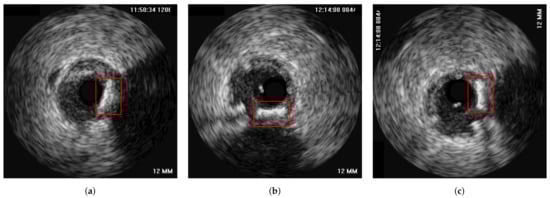

3.1. Data Preprocessing

3.3. Axial Registration